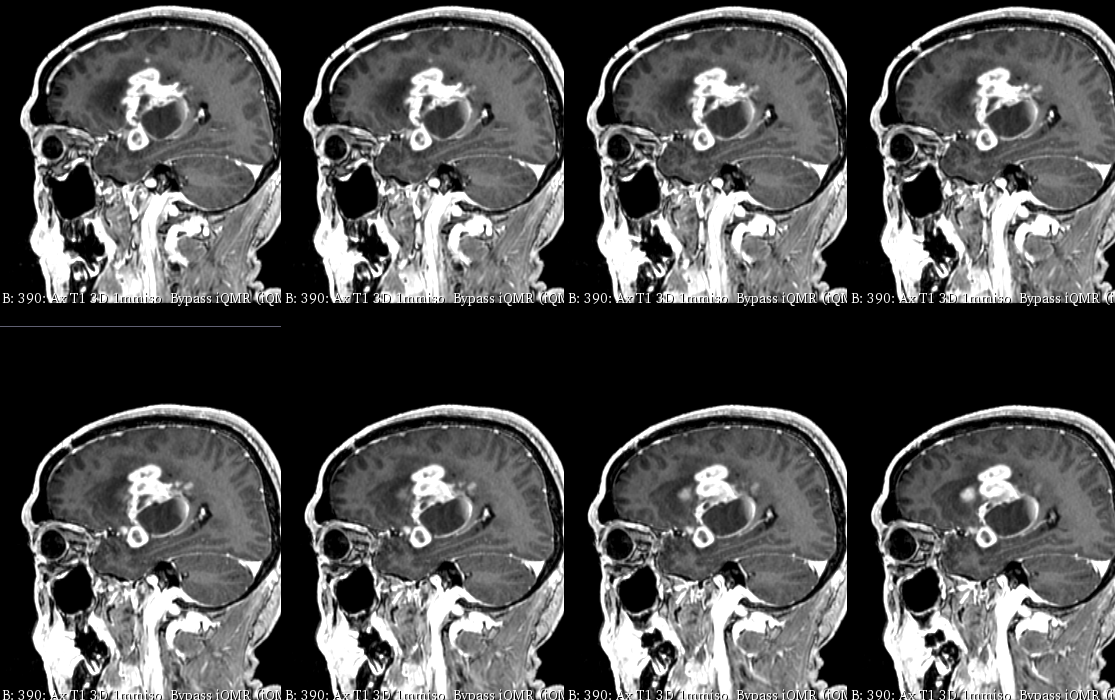

入院后于当地医院完善头颈部CTA检查未见明显血管发育异常,于2023-6-7行血肿钻孔引流术+脑室内颅内压监护探极置入术,引流一周后拔除引流管,期间未行尿激酶注射,患者反应情况逐渐好转,肌力未见明显改善。于出血后3周左右脑水肿基本消退后出院行康复治疗,治疗过程中患者肌力曾有所改善,左侧肢体肌力最好可达3级。术后3月左右患者一般状态逐渐变差,无发热,神志逐渐进展为昏睡状态,左侧肢体肌力1级,复查颅脑CT示水肿较前明显加重,颅脑MRI示右侧基底节区长T1长T2团块状病变,内有囊变,呈不均匀菜花样强化,考虑为高级别胶质瘤可能性大。遂行开颅病灶大部切除+去骨瓣减压术,术后病理提示高级别胶质瘤伴囊变,后续行同步放化疗STUPP方案,PTV:60Gy/30F/6周,替莫唑胺350mg化疗。患者右侧基底节区病灶相对稳定,2024-9-3复查颅脑MRI可见脑室内新发病灶。患者目前KPS 60分,神志清醒,精神差,反应迟钝,语言对答部分切题,右侧肢体自主活动,左侧肢体肌力2级。